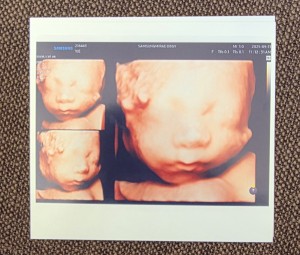

후기[28주~40주]

28주 입체초음파

닉네임_박*희_8

2025-09-18

9

2